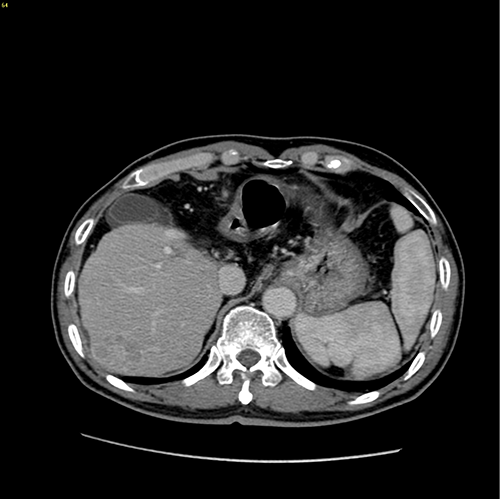

S7肝癌 门脉高压脾亢---S7切除 贲门周围血管离断